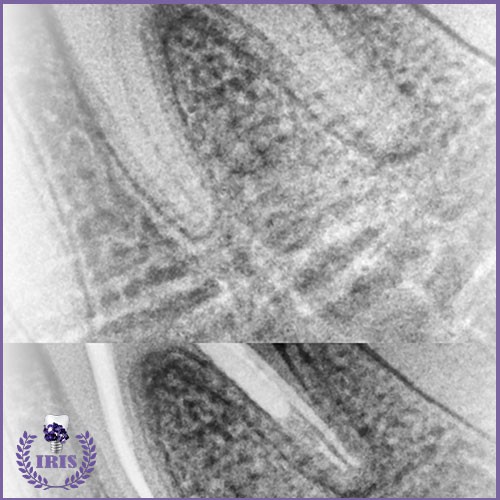

A root canal, or root canal treatment, is a medical procedure that aims to save a damaged tooth instead of extracting it. When a tooth decays deeply, the decay reaches the pulp of the tooth, which contains the nerves and blood vessels. In this case, the dentist removes the affected part of the nerve, cleans the root canals, and then fills them with a special material to prevent the spread of infection and protect the tooth.

Root canal cleaning: The root canals are carefully cleaned to remove bacteria and infected tissue.

Filling: The root canals are filled with a special material.